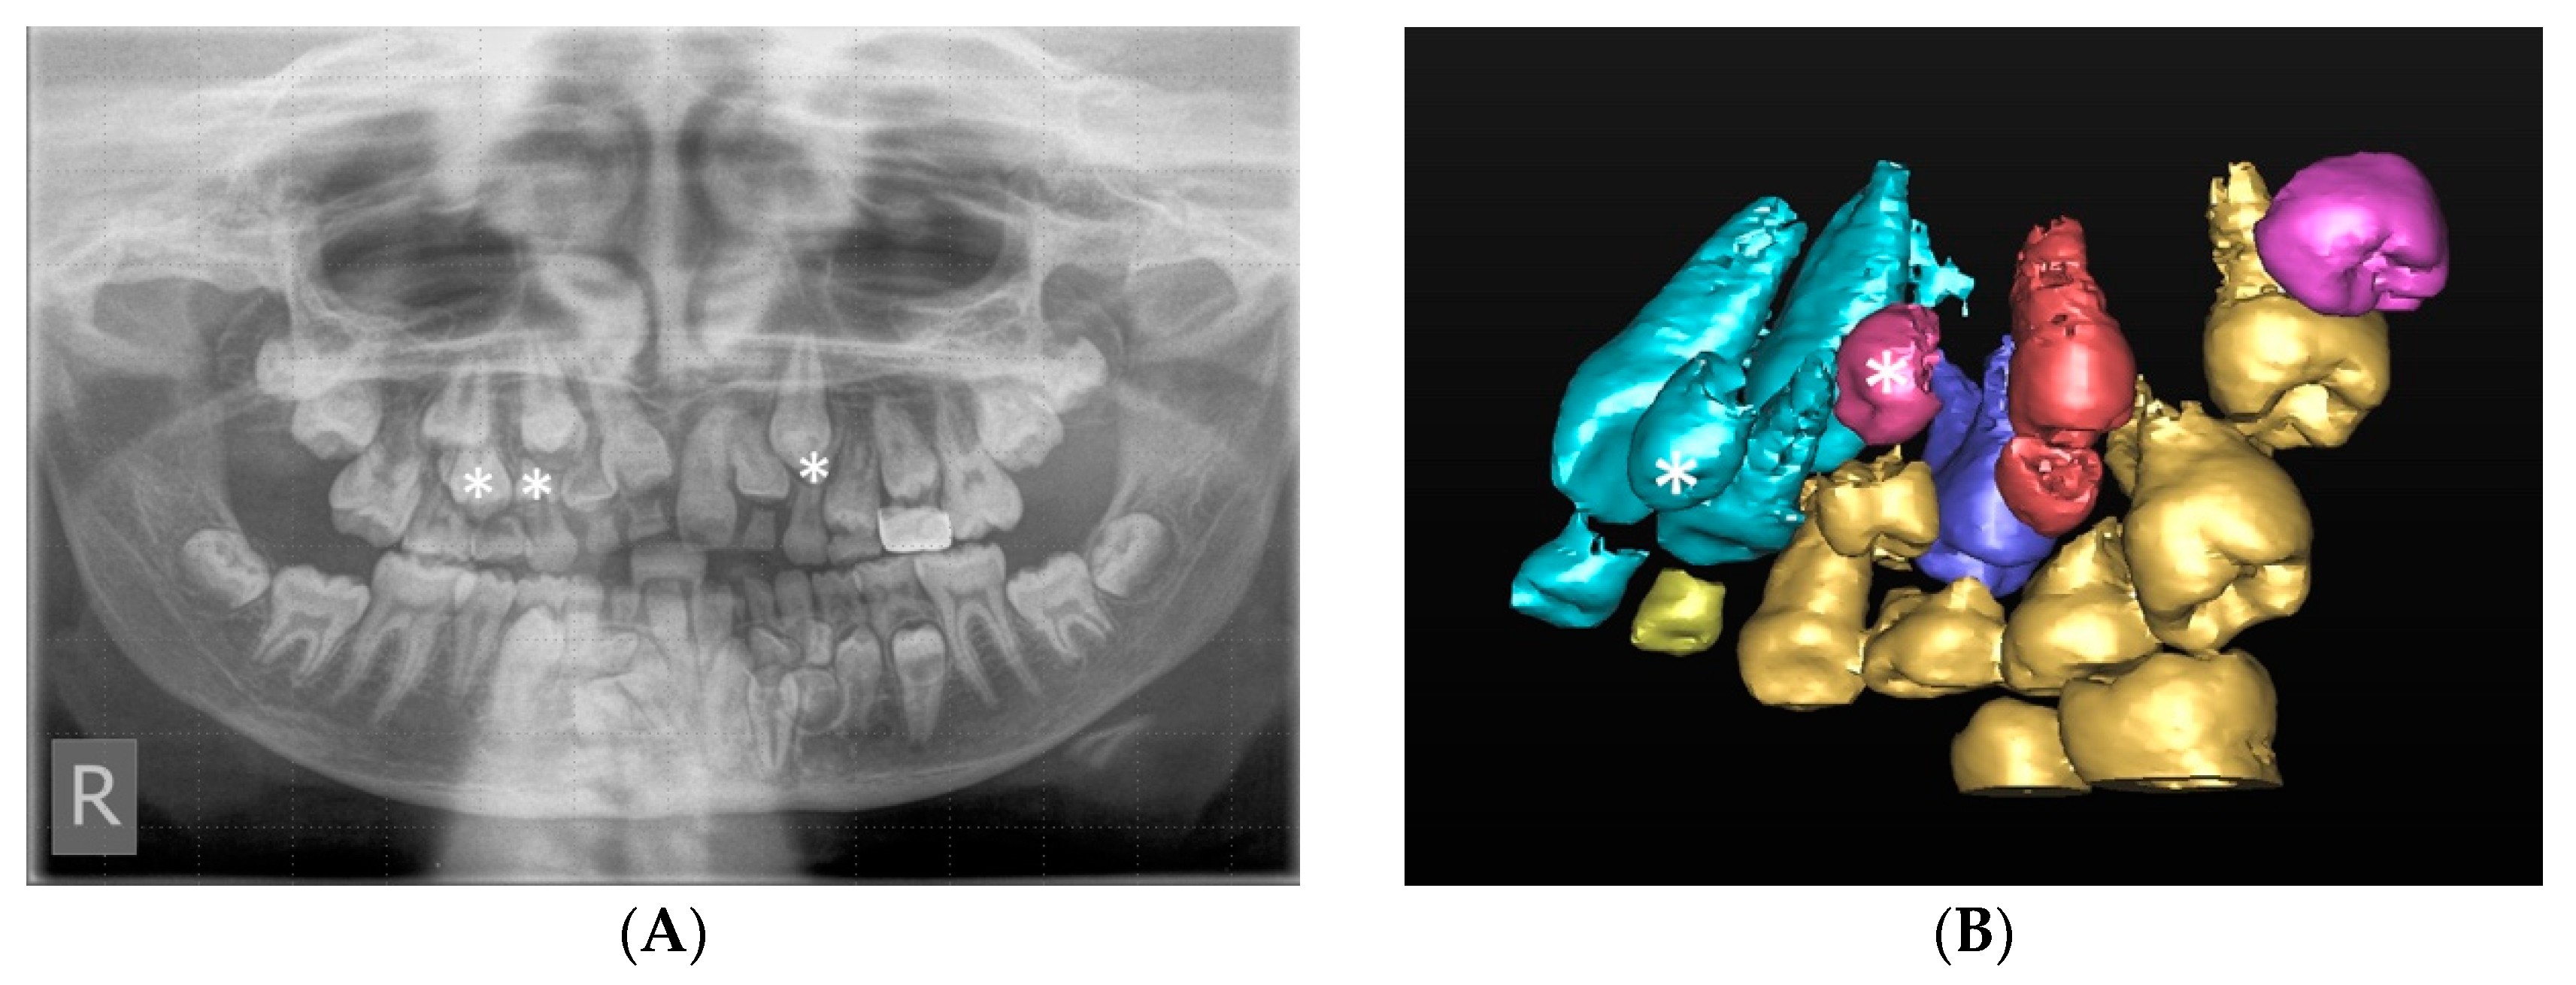

Indeed, there were multiple cases where a greater number of unerupted supernumeraries was detected following CBCT assessment and, therefore, helped avoid treatment errors. Figure 3 illustrates a case where four additional supernumerary teeth could be located on the CBCT that were not detected on the panoramic view and would have been missed. Superimposition of the anatomical structures on conventional scans could affect the management of the case as a whole and possibly result in a repeat general anaesthetic for the patient in the future.

Figure 3.

(A) Panoramic radiograph demonstrating multiple supernumerary teeth in the maxilla and mandible. There are three clearly visible supernumerary teeth in the maxilla (marked with asterisks. (B) Three-dimensional (3D) segmented reconstruction of the right maxilla viewed from the palatal aspect showing two further maxillary supernumerary teeth marked with an asterisk, one palatal to the upper right central incisor and the other palatal to the upper right canine (©DentsplySirona-Simplant® Pro).